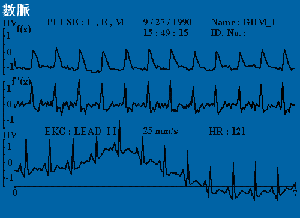

脈診波形

代脈_0020765003

平脈_0020765001

弦脈_0020765002

弦滑脈_0020765004

促脈_0020765001

洪脈_0020765002

細脈_0020765002

結脈_0020765004

滑脈_0020765001

數脈_0020765005

遲脈_0020765005

澀脈_0020765001

濡脈_0020765003